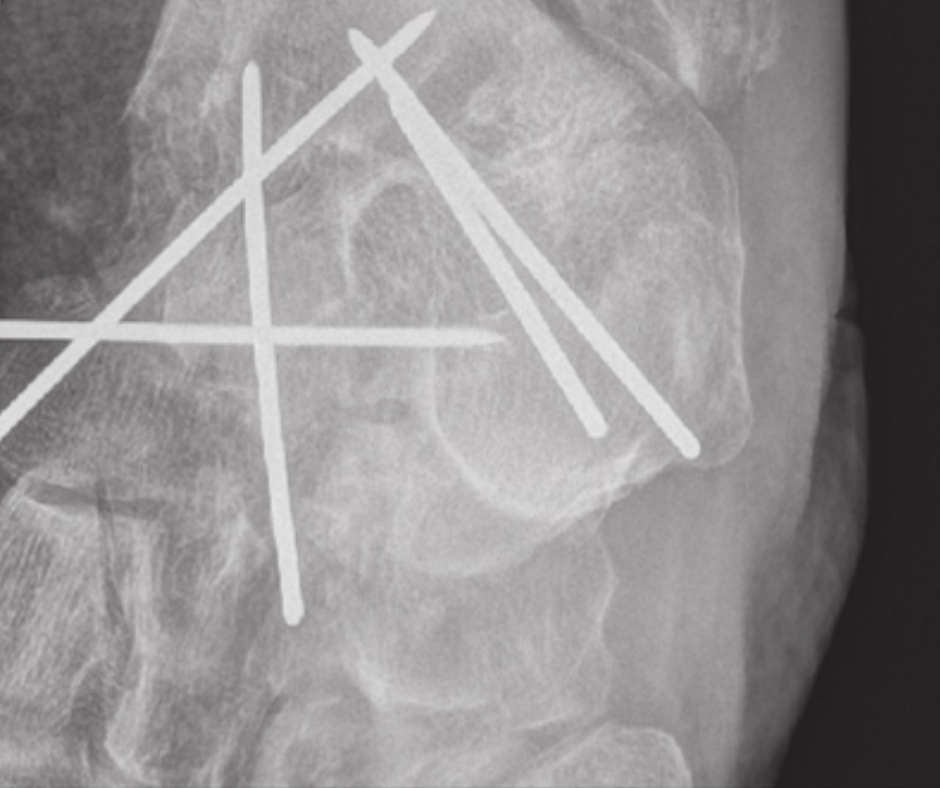

Identifying these easily missed breaks can save patients from future negative complications or loss of function.

Code is for vertebral compression fracture detection with CT scans.